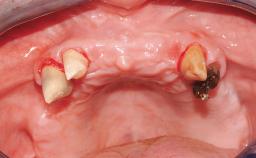

A 63-year-old male patient was referred for a consultation and treatment of partial edentulism in the maxilla. The patient presented with residual anterior teeth and declined a partial removable prosthesis. He reported that the maxillary posterior teeth had been extracted due to mobility and periodontal disease two months before the consultation. The patient’s chief complaint was that his residual maxillary teeth were mobile and that he was unable to chew. The patient’s desire was a stable and comfortable fixed maxillary rehabilitation. The patient was a light smoker (fewer than 10 cigarettes/ day), and his medical history was without significant findings. He was not on any regular medication at the time of consultation. The extraoral examination revealed a normal physiognomy with a correct distribution of the facial thirds. The patient presented a low lip line, and the transition line between teeth and soft tissues was not exposed during a forced smile.

Case Type Edentulous Maxilla

Defining Characteristics Fully edentulous upper jaw to be rehabilitated with four or more implants

Bone Volume Horizontally and vertically sufficient